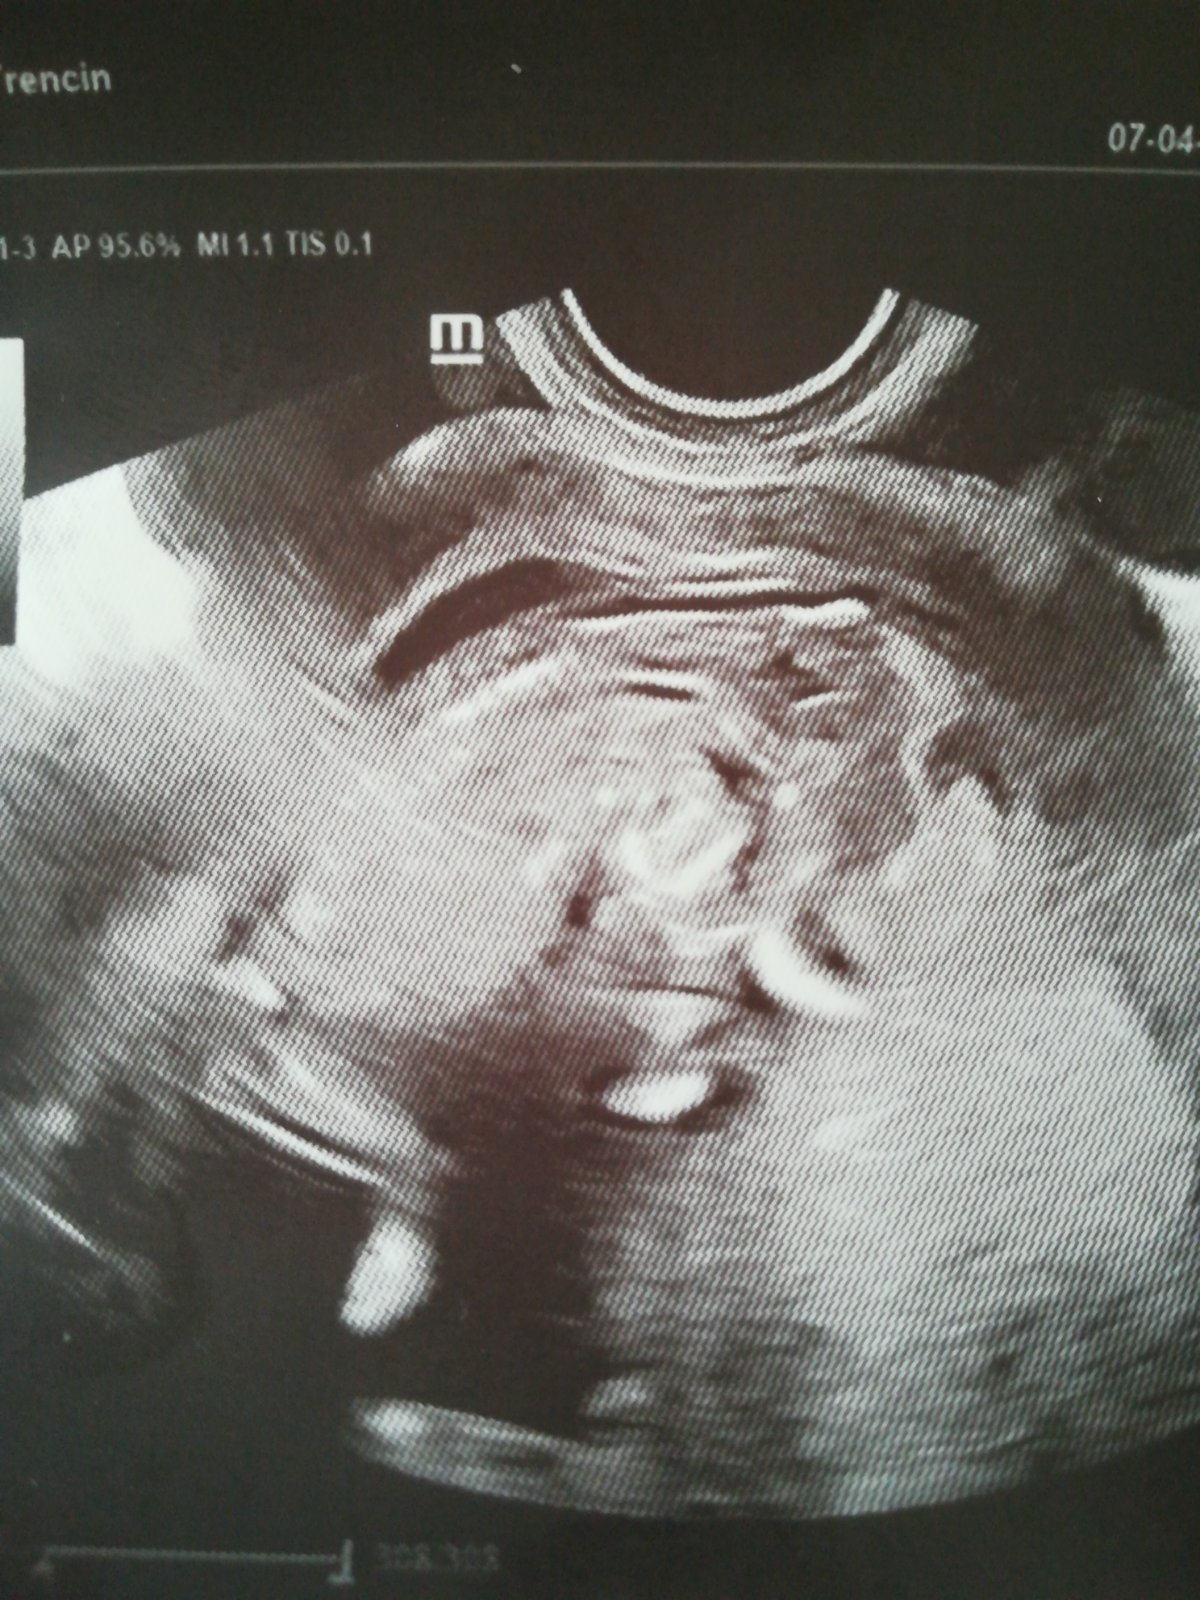

Babo je z boku, takze nevidno medzi nozicky. Podla tejto fotky by to neurcil ani lekar.